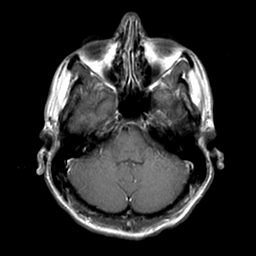

Sarcoma, MR Study #1 mr-gad -- Slice #4

[Home][Help][Clinical] Slice 4